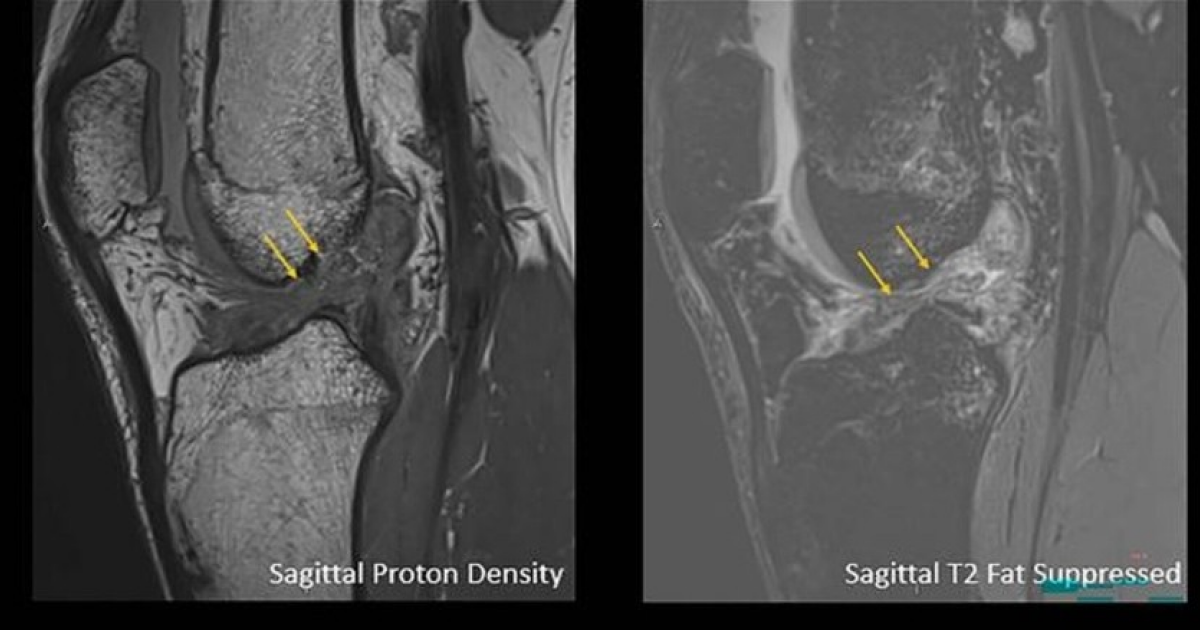

Рентгенологи заметили гендерную разницу в травмах коленей Рентгенологи проанализировали результаты 13549 магнитно-резонансных томограмм коленных суставов пациентов, жалующихся на боль в коленях, и выявили до …